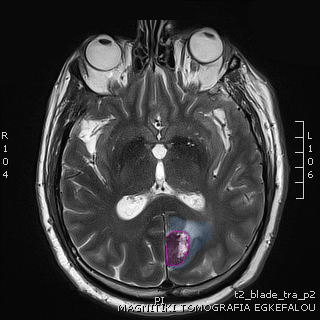

Περιγραφή Η επέμβαση μπορεί να γίνει υπό τοπική ή, συχνότερα, γενική αναισθησία. Υπάρχουν 2 τρόποι να πραγματοποιηθεί η εντόπιση της εξεργασίας: ο πρώτος είναι με τη βοήθεια στεροτακτικού πλαισίου από τιτάνιο το οποίο στερεώνεται στο κρανίο του ασθενούς με ειδικές βίδες και ο δεύτερος με την βοήθεια νευροπλοήγησης, χωρίς εξωτερικά εντοπιστικά βοηθήματα. Και στις 2 περιπτώσεις πραγματοποιείται μια μαγνητική τομογραφία εγκεφάλου προεγχειρητικά για τον σχεδιασμό της επέμβασης (σημείο εισόδου και τροχιά της βελόνης). Η λήψη της βιοψίας γίνεται μέσω κρανιοανάτρησης (διάνοιξη μικρής οπής στο κρανίο) και με τη βοήθεια ειδικής βελόνης με κοπτική θαλάμη η οποία εισέρχεται στον εγκέφαλο προκειμένου να ληφθούν τεμάχια της εξεργασίας. Από την ίδια βελόνη μπορεί να αφαιρεθεί υγρό για κυτταρολογική εξέταση ή καλλιέργεια. |

Όγκος εγκεφάλου με περιβάλλον οίδημα. |